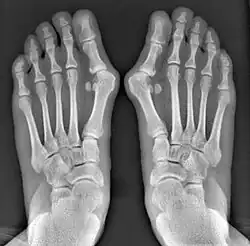

- For recurrence correction after osteotomy procedure (Fig. 8)

Late deformity recurrence can happen after osteotomy (bone-breaking) procedures because osteotomy surgeries do not specifically stabilize first metatarsal bone.